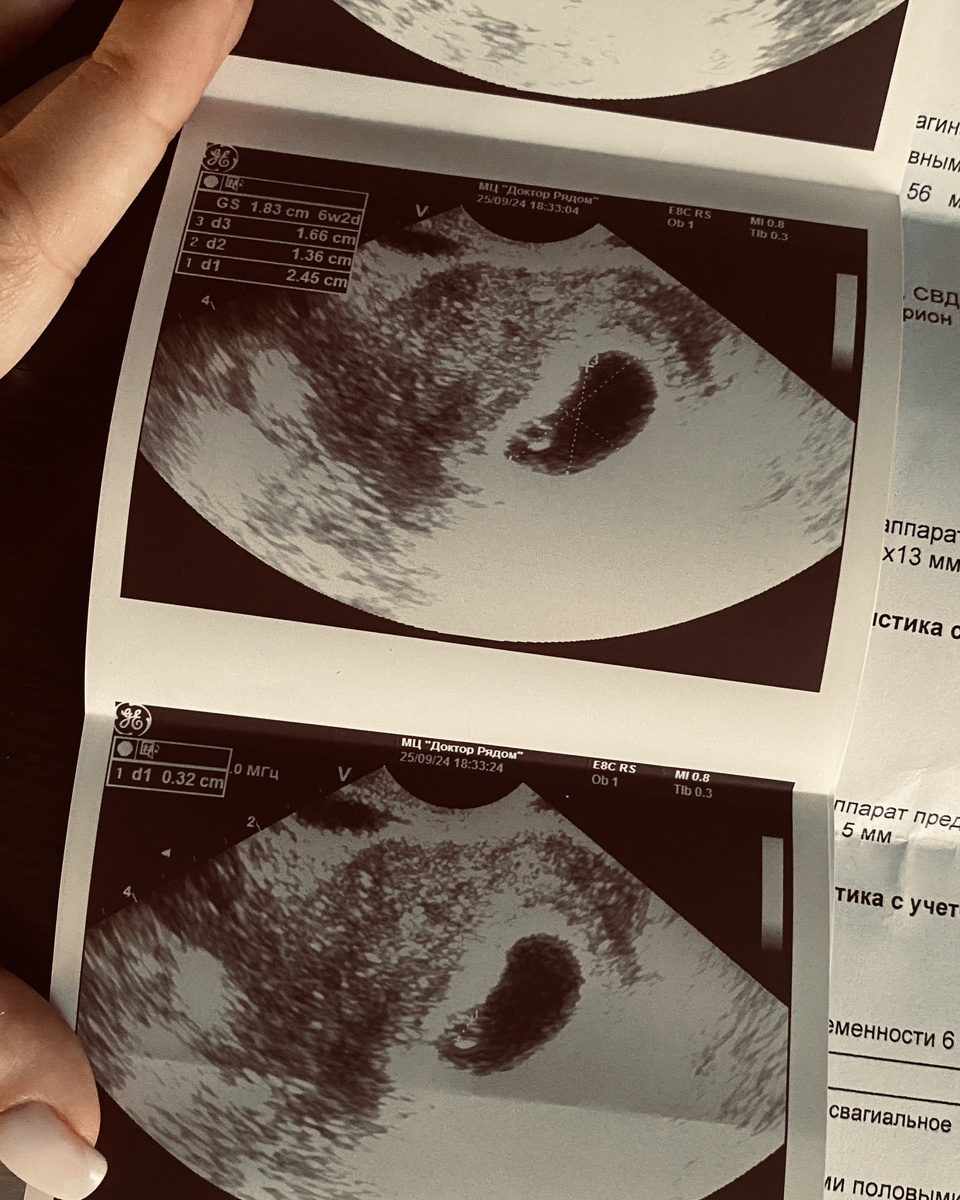

На 6 неделе я услышала сердечко 🫀

Маленькое. Быстрое. Внутри меня. Но не моё.

И в ту секунду всё тяжёлое отступило. Я просто лежала и слушала.

И получила свой первый снимок с еще тогда эмбрионом, который в будущем станет малышом. Он был еще маленьким, мало, что было понятно. Но сердце понимало - это мое. Родное.

Тогда я впервые по-настоящему почувствовала: нас уже двое.🤰🏼

Наше первое УЗИ. Тогда это было просто маленькое плодное яйцо, но для нас — уже целый мир.